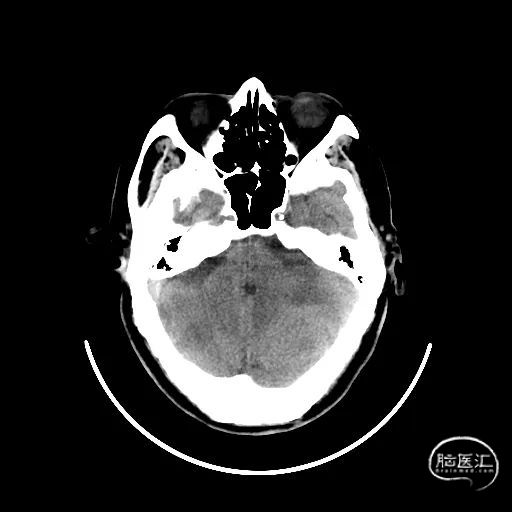

支架释放:

释放4mm*25mm Neurohawk取栓支架,可见支架显影良好,支撑性好,远端打开良好。中间导管跟上抽吸-SWIM技术。

操作要点:

固定支架推送杆,缓慢回撤支架微导管。